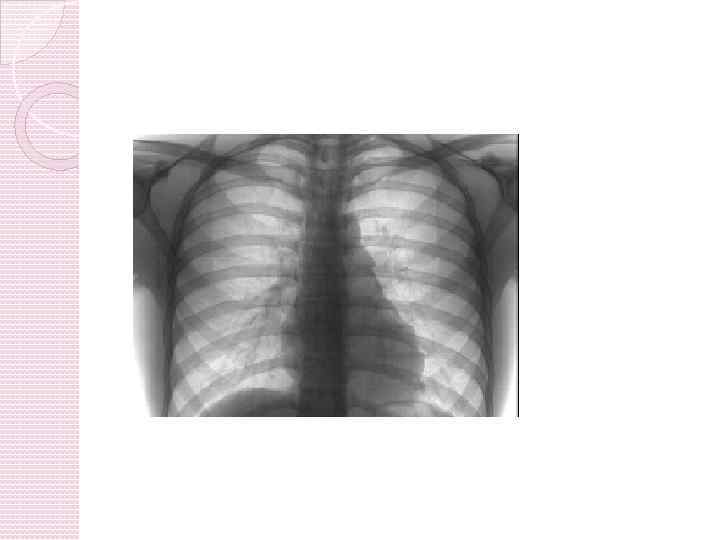

инструментальные Бронхоскопия. Бронхография. Рентгеноскопия и рентгенография легких. Исследование функции внешнего дыхания. Исследование газового состава крови.